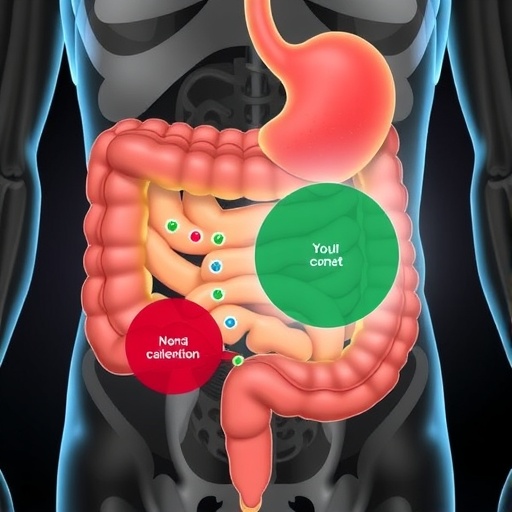

Fusobacterium nucleatum, an anaerobic bacterium increasingly recognized for its role in colorectal cancer (CRC), has taken center stage in groundbreaking research that elucidates how this microorganism adheres to cancer cells. This interaction, pivotal in the progression of CRC, has long puzzled scientists due to its complexity and the bacterium’s ability to both colonize tumor microenvironments and suppress immune responses. Now, a collaborative study led by Professor George F. Gao’s team at the Institute of Microbiology, Chinese Academy of Sciences (CAS), reveals the intricate molecular mechanism behind this adhesion, offering a promising avenue for targeted cancer therapies.

The bacterium’s capability to bind to human cells is mediated by a specialized surface protein called CbpF, an autotransporter adhesin, which recognizes and binds to CEACAM1 and CEACAM5. These two cell surface receptors are often overexpressed in various cancers, providing an opportunistic docking platform for F. nucleatum. CEACAM1’s role is particularly notable, as it functions not only as an adhesion receptor but also as an inhibitory immune receptor, dampening immune cell activity once engaged. This dual functionality underscores the bacterium’s sophisticated strategy to both anchor and evade host defenses, a phenomenon that until now lacked detailed structural insight.

The implications of this discovery extend beyond a mere structural curiosity. Since CEACAM1 engagement suppresses immune activation, F. nucleatum’s binding could directly contribute to immune evasion within the tumor microenvironment, promoting cancer progression and resistance to therapy. Therefore, targeting the CbpF-CEACAM interaction presents an attractive therapeutic strategy to disrupt this malignant crosstalk. Small molecules or antibodies that interfere with the binding interface could restore immune surveillance and hinder bacterial colonization on tumor cells.

As colorectal cancer remains a leading cause of cancer-related mortality worldwide, insights into microbial contributions to tumor biology could shift paradigms in oncological treatment. The identification of bacterial factors like CbpF that modulate tumor-immune dynamics provides a fresh perspective on managing cancers traditionally viewed through a solely human genetic lens.